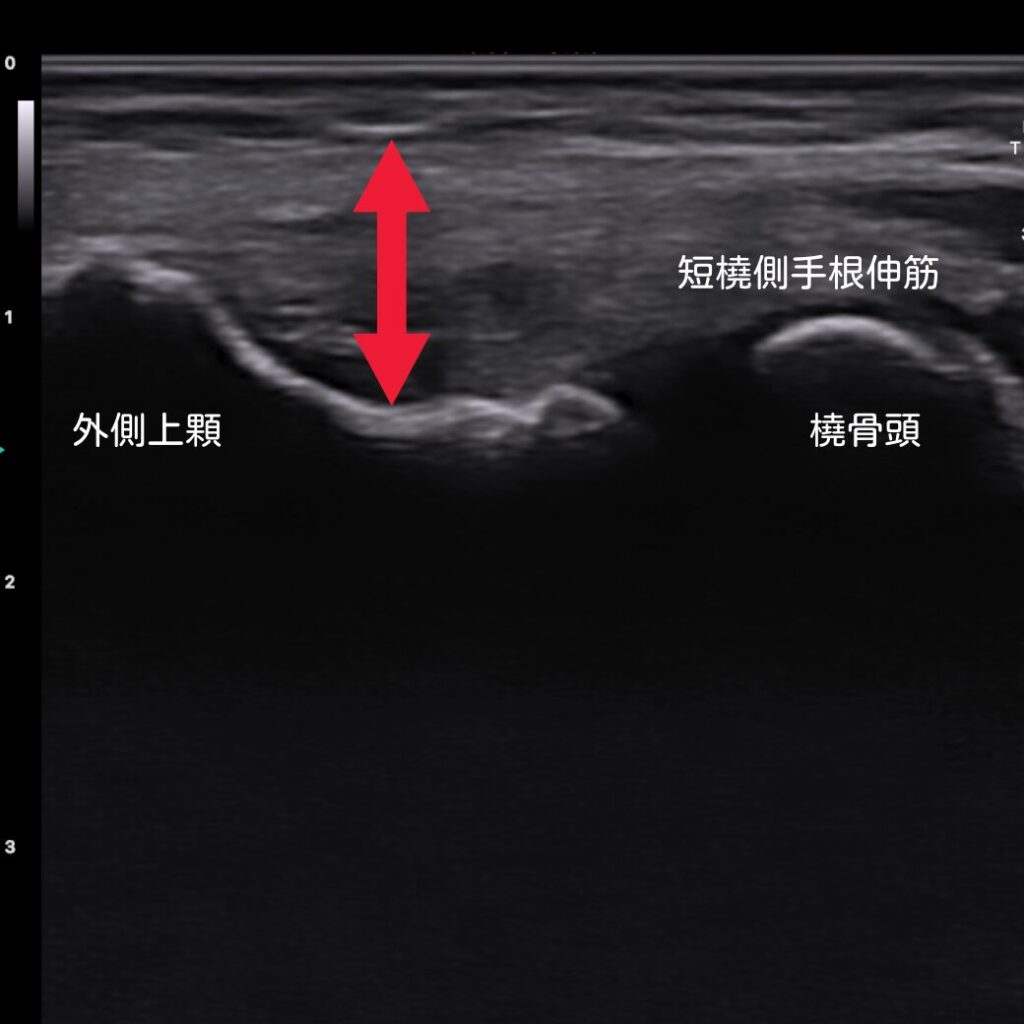

エコーで患部を「見える化」

当院では、超音波エコーを活用し、腱の付着部や肥厚の状態をリアルタイムに左右比較しながら観察できます。これにより、痛みの原因をより正確に把握し、最適な施術プランを立てることが可能になります。

エコー確認で、腱の厚みの違いが明らかになります。合わせて炎症状態も確認が可能です。